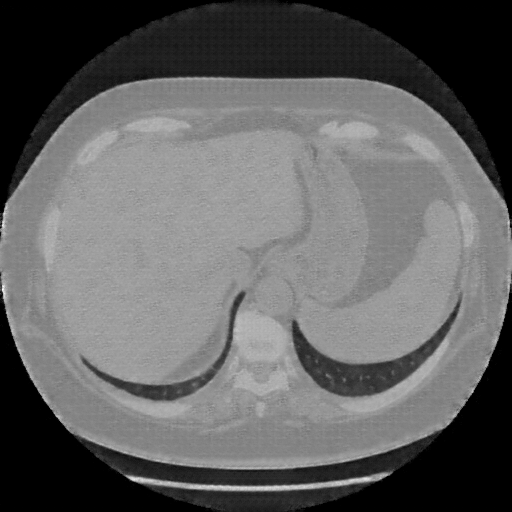

Generated VENOUS CT scan (A→B translation)

Full window (WL 1023.5, WW 4095 β†’ Low βˆ’1024, High +3071)

Mediastinum window (WL 40, WW 400 β†’ Low βˆ’160, High +240)